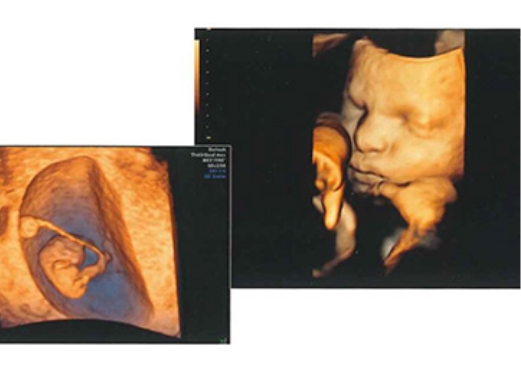

また、妊娠中の不安や体調の変化などについてご相談いただけるよう、助産師によるカウンセリングを実施しております。健診では4D超音波診断装置(追加費用はかかりません)を用い、赤ちゃんの様子を立体的に確認できる機会も設けています。

4D超音波診断装置(追加費用なし)

お腹の赤ちゃんの様子を立体的にご確認いただける4D超音波診断を、追加費用なしで実施しています。条件がよければお顔やしぐさなどが見えることもあります。健診では、赤ちゃんの心拍なども医師が丁寧に確認しています。